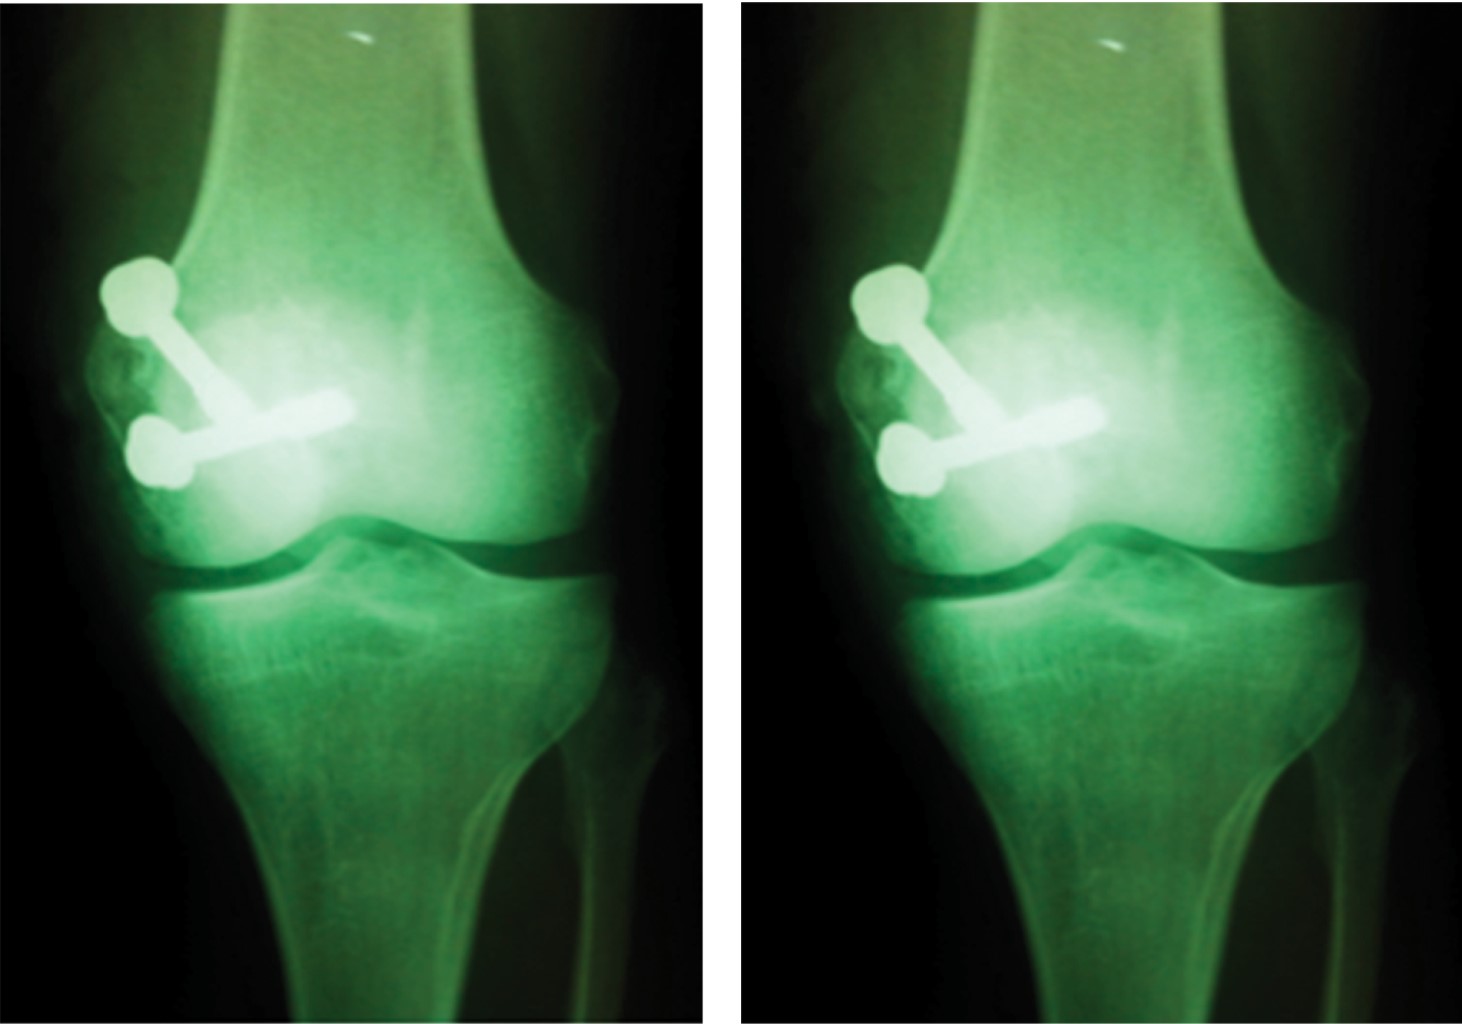

Introduction: knee femoral condyle coronal fractures or Hoffa fractures are among the rarest fractures of the pelvic limb, being even more rare those of the medial condyle. The success in the management of these patients lies in the timely diagnosis and the consequent anatomical reduction of the femoral articular surface. Clinical case: the objective of this article is to present a patient with right medial Hoffa fracture, registered as a single case in the archives of our hospital. The patient was referred to us on November 2011, with a 10-day course after suffering a fall from horse ridding, presenting a forced varus mechanism and direct contusion of the right knee. He shows an anteroposterior and lateral knee X-rays showing a subtle solution of continuity in the coronal plane of the base of the medial condyle, corroborated with magnetic resonance imaging and was also associated with a non-surgical partial injury of both menisci and the anterior cruciate ligament. Surgical intervention was performed on 27th/11/2011, through open reduction with a medial approach and internal fixation with 7.0 mm (x2) cannulated screws. The patient was discharged with early and continuous mobilization of the knee, deferring support and rehabilitation until the 6th week. He is currently a wandering patient, asymptomatic, with complete range of motion. Because respecting the extensor apparatus through a medial approach and the articular surface with cannulated screws, it was observed in consequence an adequate evolution of our patient, being able to return to his daily activities, even remount.

Figure 2

Figure 3